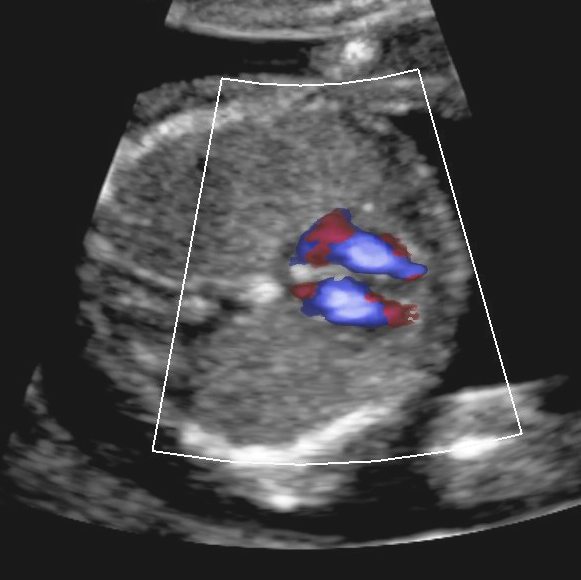

Vierkammerblick

Button

Bildtitel

13. SSW: Fünfkammerblick

Pulmonalisblick